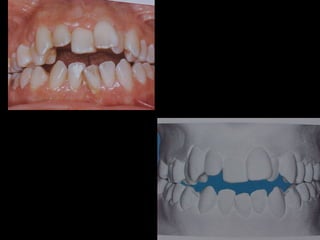

Marcada Clase III

Hábito Lingual

Sobremordida horizontal: –1.5 mm

Sobremordida vertical: + 1 mm.

Frente:

Línea media desviada

Mordida cruzada anterior

La paciente fuemanejada iatrogénicamente por 5 años Utilizando diferentes implementos ortodóncicos La regla es clara: Laterognatias de más de 2º son quirúrgicas

La paciente muestrauna franca disgnatia, clínicamente observamos malposición dentaria secundaria a la falta de armonía máxilomandibular. La paciente muestra una franca disgnatia, clínicamente observamos malposición dentaria secundaria a la falta de armonía máxilomandibular.

Marcada Clase III HábitoLingual Marcada Clase III Hábito Lingual Sobremordida horizontal: –1.5 mm Sobremordida vertical: + 1 mm. Sobremordida horizontal: –1.5 mm Sobremordida vertical: + 1 mm.